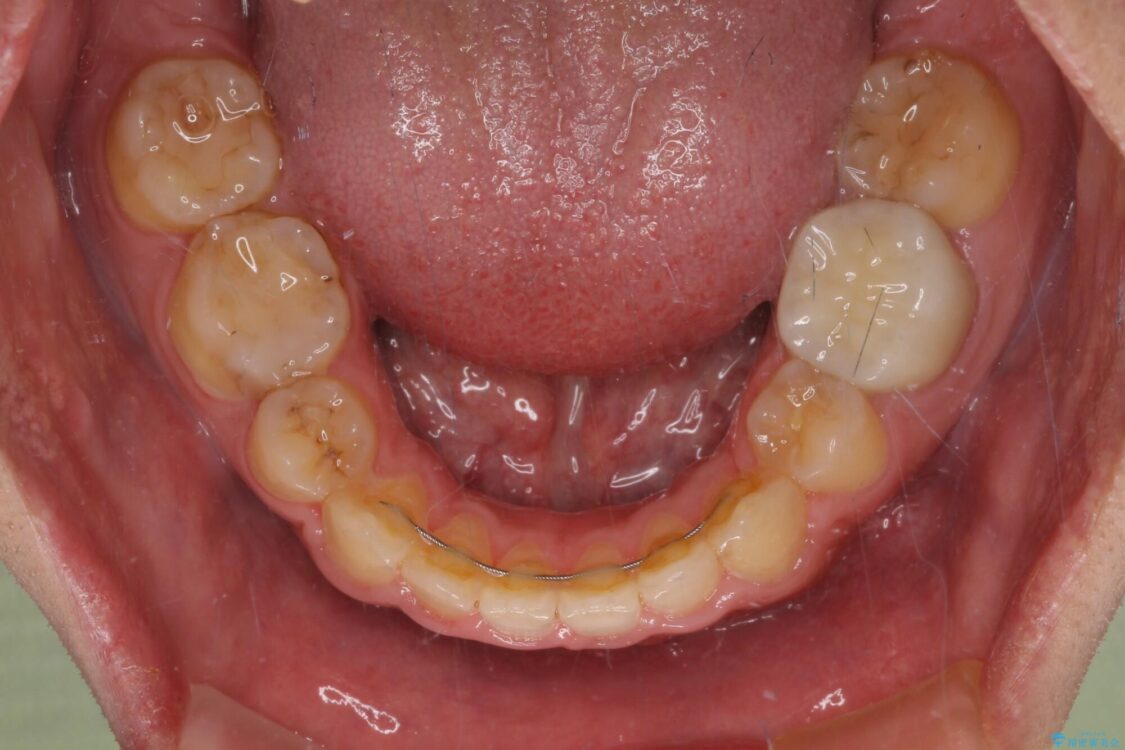

治療前

• 後戻りでデコボコの前歯 インビザライン矯正治療 治療前画像